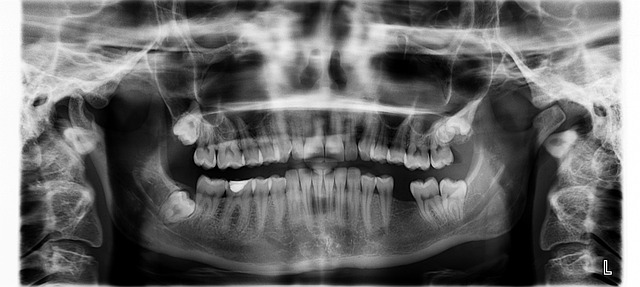

The research utilized a large dataset of orthopantomograms (OPGs), which were meticulously labeled by dental experts according to the Demirjian system. The dataset comprised images of both left and right lower jaws, resulting in a substantial collection for model training and evaluation. To enhance the accuracy and robustness of the system, several key techniques were employed:

- Region of Interest (ROI) Extraction: The OPGs were carefully cropped to isolate the regions containing the third molars, minimizing irrelevant information and focusing the model’s attention on the crucial areas.